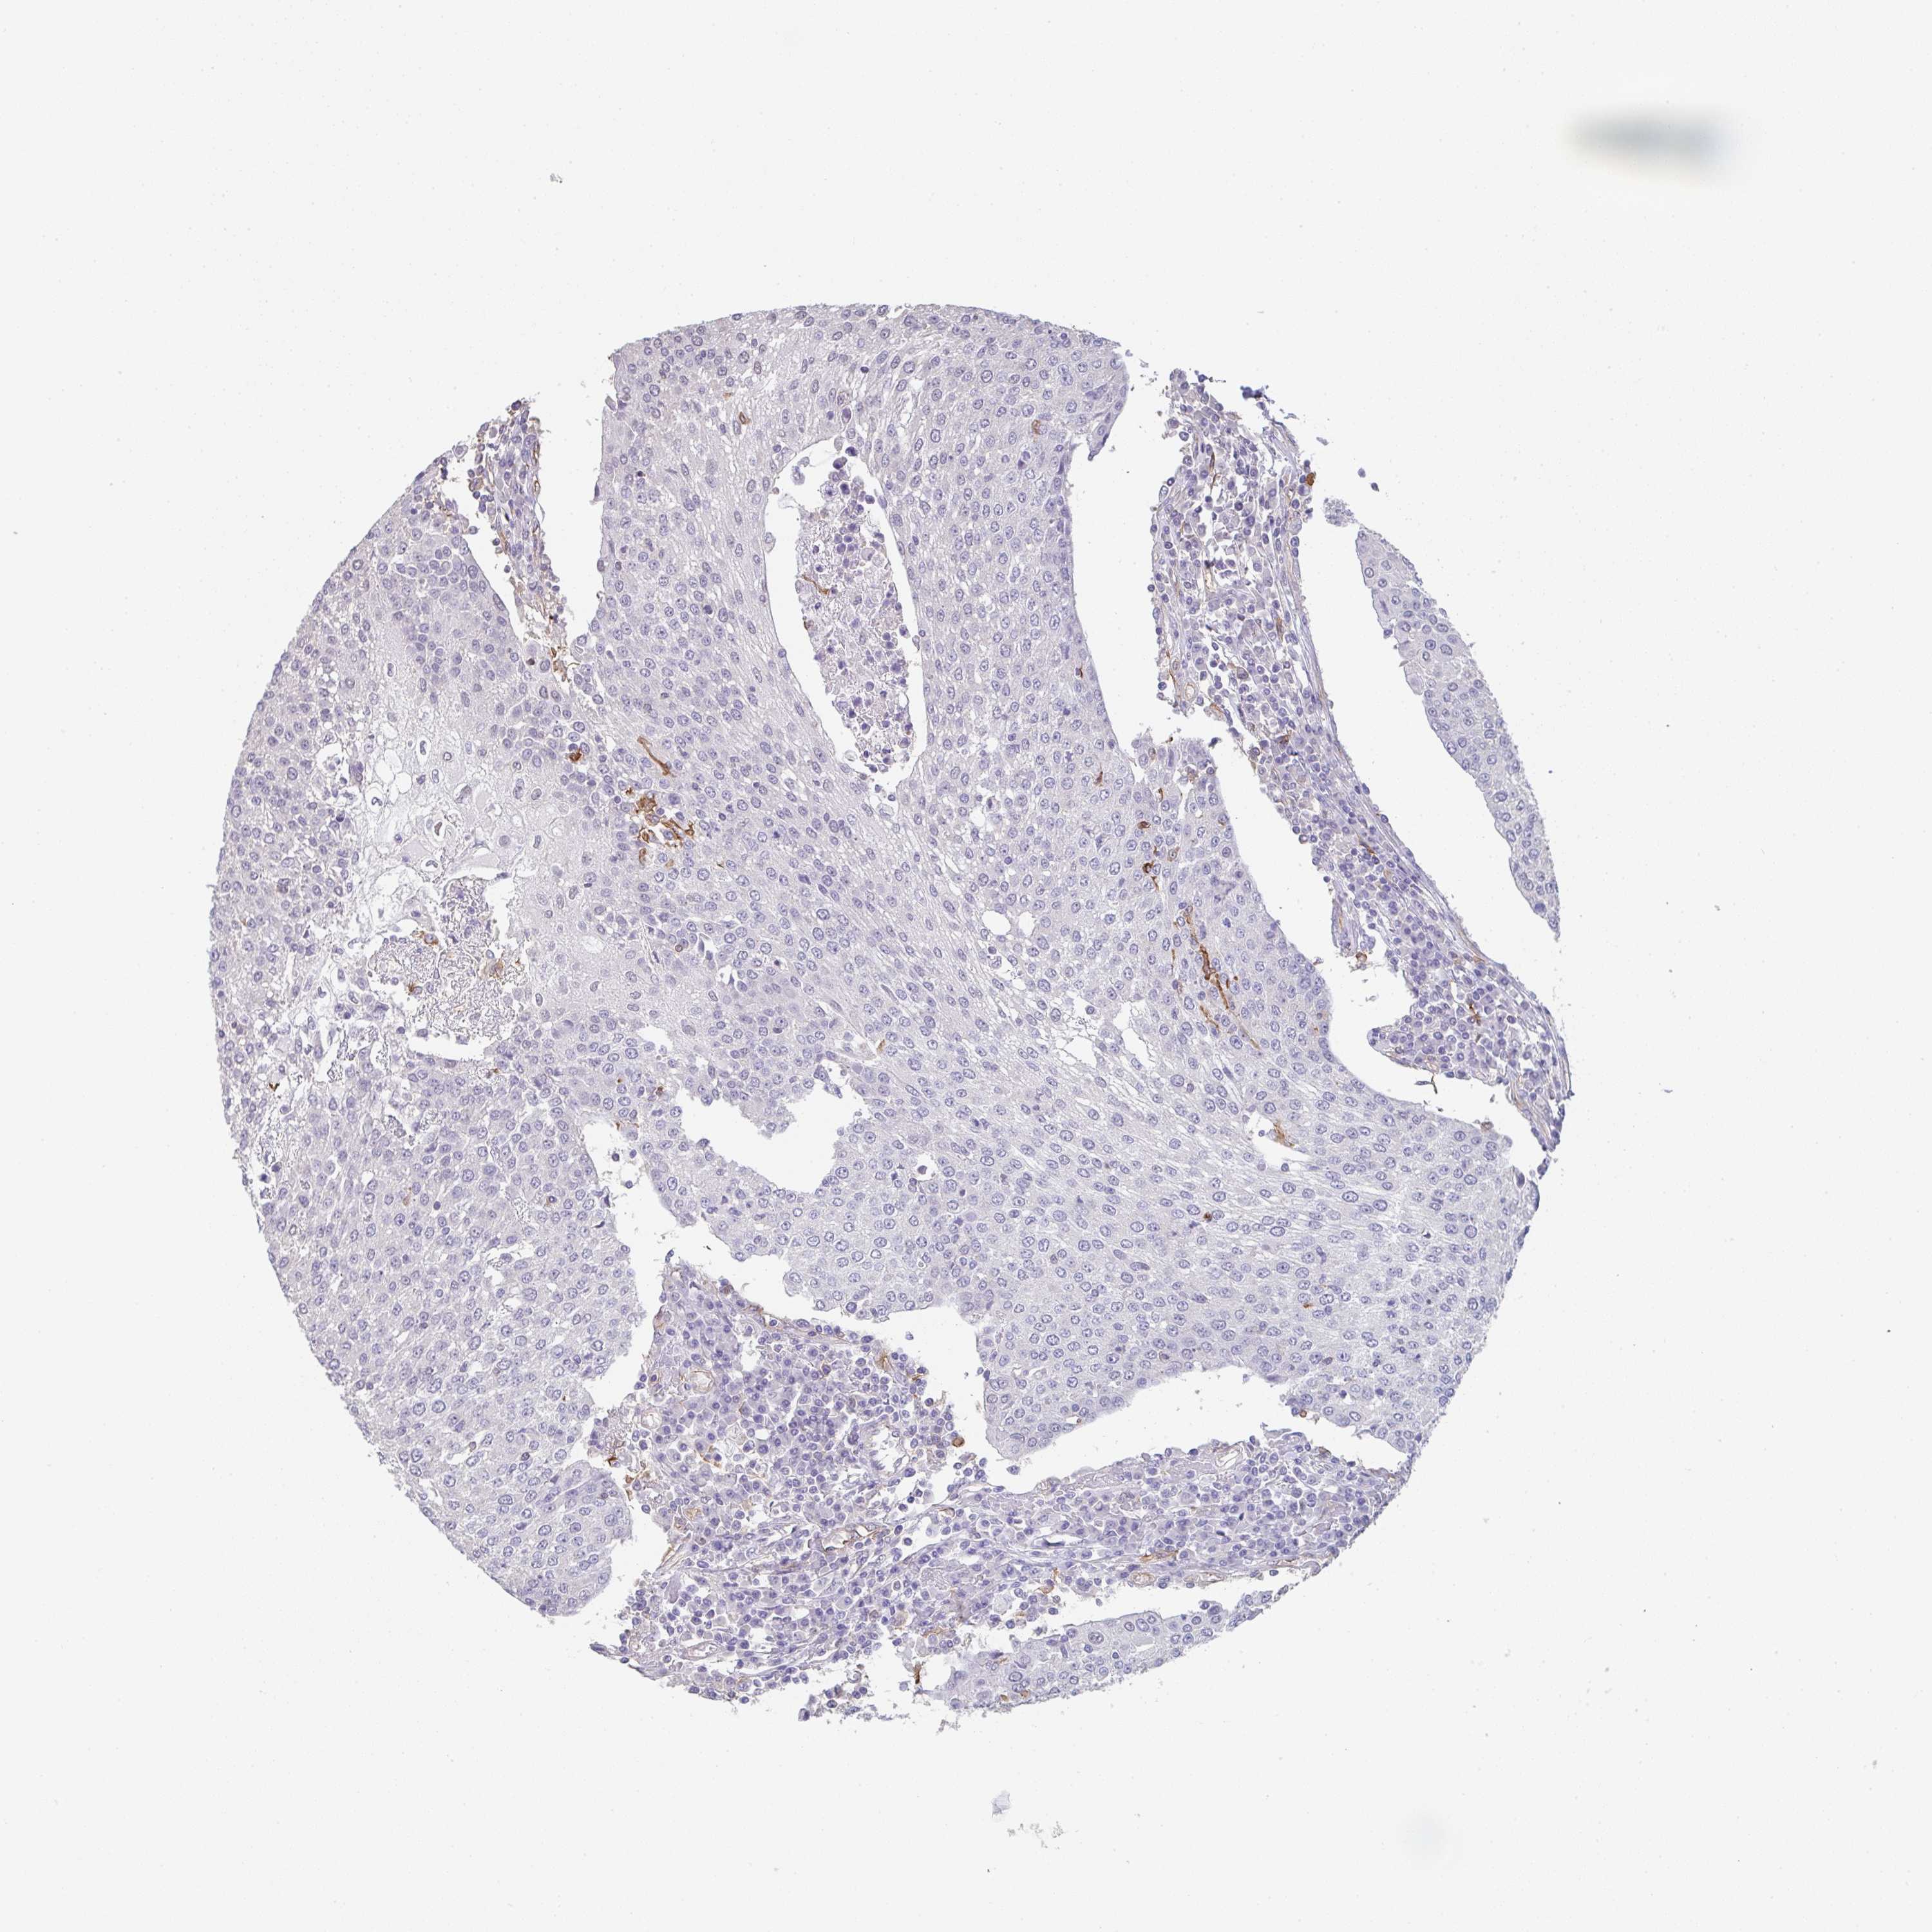

UROTHELIAL CANCER - Protein expressioni

A mouse-over function shows sample information and annotation data. Click on an image to view it in a full screen mode. Samples can be filtered based on level of antibody staining by selecting one or several of the following categories: high, medium, low and not detected. The assay and annotation is described here.

Note that samples used for immunohistochemistry by the Human Protein Atlas do not correspond to samples in the TCGA dataset.

Antibody stainingi

Antibody staining in the annotated cell types in the current human tissue is reported as not detected, low, medium, or high, based on conventional immunohistochemistry profiling in selected tissues. This score is based on the combination of the staining intensity and fraction of stained cells.

Each image is clickable and will lead to virtual microscopy that enables deeper exploration of all samples and also displays staining intensity scores, fraction scores and subcellular localization as well as patient and tissue information for each sample.

Antibody HPA051452

Antibody HPA056940

Urothelial carcinoma, High grade

Urothelial carcinoma, Low grade